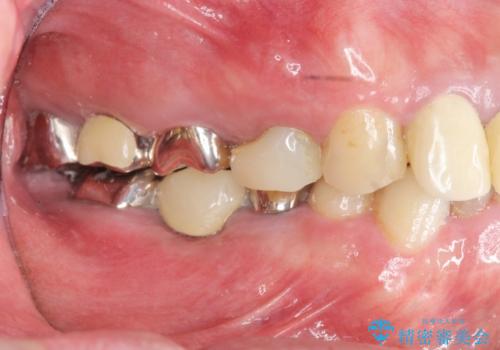

- 「少しずつ色々な箇所が悪くなり、歯医者に通い続けている。全ての歯を長持ちするような状態にできるような治療を受けたい。」、と全顎・総合的な治療を希望され来院されました。

根管治療・矯正治療・歯周外科・セラミック補綴を含む様々な治療オプションを駆使し、長期間良好な状態に保てるような治療計画を立案します。

矯正治療を絡めた総合的な治療をお行なったことで、理想的な咬合関係を確立し安定した噛み合わせで仕上げることができました。

また歯周外科を行うことで歯ぐきの腫れを改善し、清掃性を高めています。